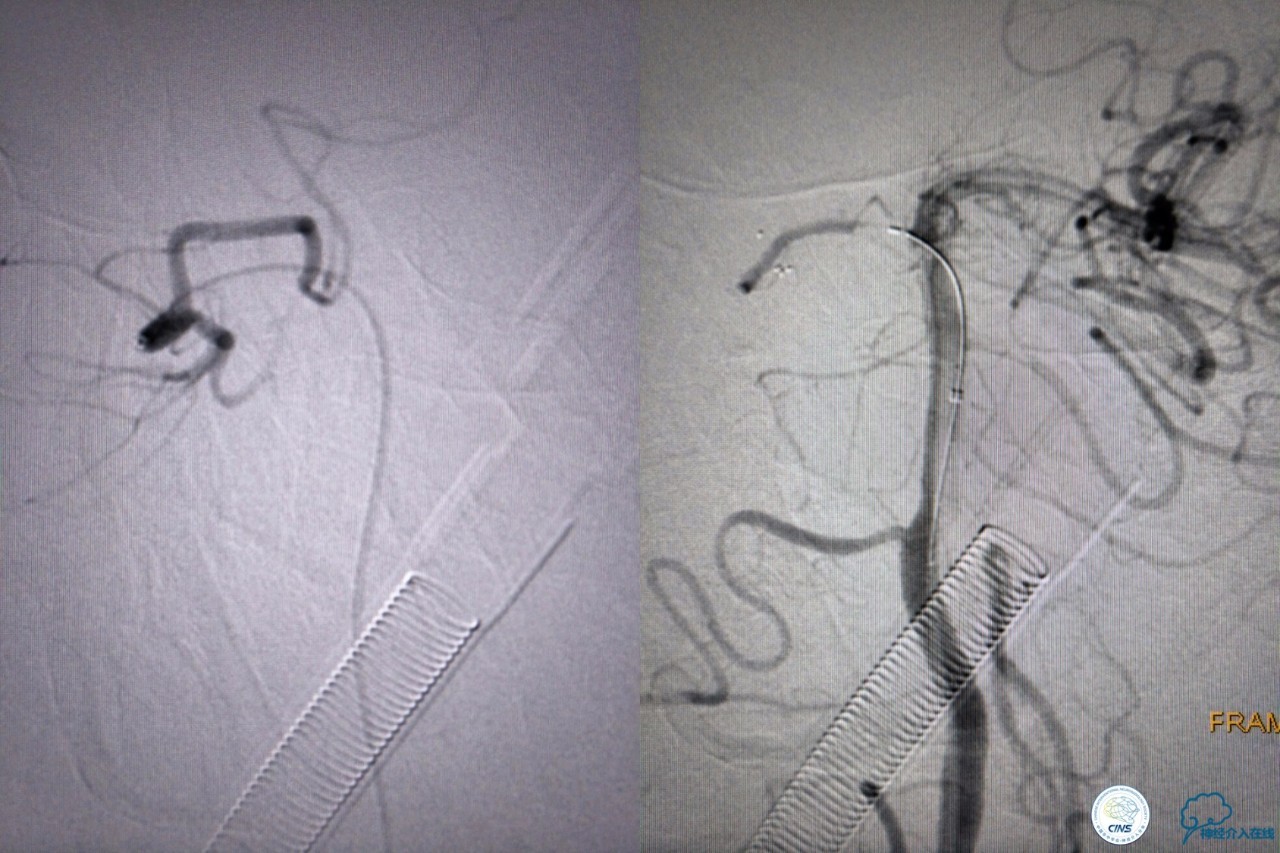

第二次取栓后可见基底动脉顶端仍有大量血栓,右侧大脑后动脉开通,但左侧大脑后未见显影且左侧小脑上动脉闭塞!

第三次取栓,支架放入左侧大脑后取栓。

第三次取栓后,左侧大脑后动脉开通,但是栓子再次栓塞右侧大脑后动脉,血栓在基地动脉顶端来回左右摆动,下一次,怎办?血栓负荷太多,可以使用solumbar技术,可以没有颅内导管,没办法,换用更大的支架6-20mm,但费用增加不少,与家属沟通后同意使用,第四次取栓:

血栓负荷还是很大,左侧大脑后再通,但右侧大脑后又闭塞,只能第五次取栓,支架放到右侧大脑后动脉更远。

好大的血栓,支架释放后,血管无复流,拉一把!

没错,没看错!血管成功实现再通,术中取栓的栓子如下。